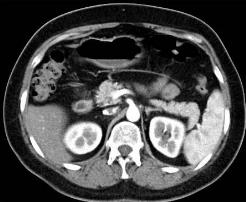

胸部CT检查提示:左肺癌术后,纵隔向左移位,左肺体积缩小,其内见多发斑片索条影,左侧胸膜增厚,前胸壁见大小约3.0x3.6cm团块状影,边缘不 整,部分肋骨及心包受侵。左前胸壁考虑:转移瘤可能。